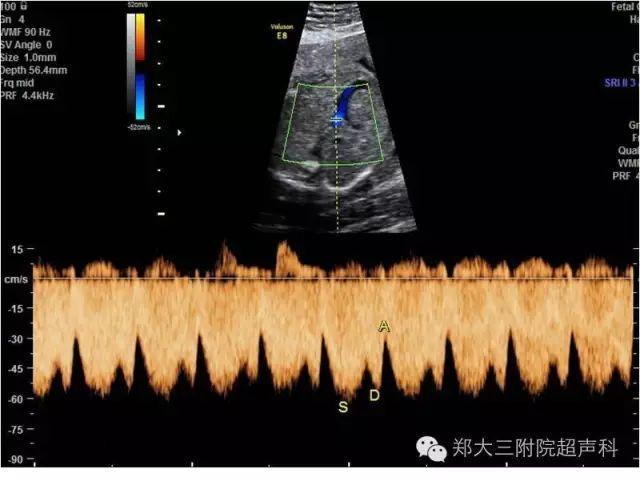

胎儿静脉导管频谱图片,胎儿静脉导管超声图

孕早期超声扫查规范(fmf 版):静脉导管血流

中晚孕期正常胎儿静脉导管血流频谱分析

胎儿静脉导管血流频谱